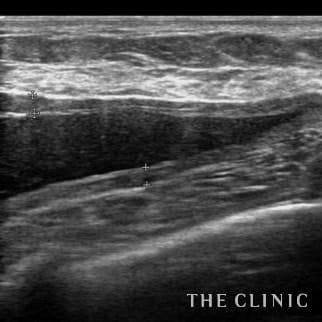

50歳 女性 アクアフィリング(アクアリフト)豊胸のお悩みのアクアフィリング(アクアリフト)豊胸除去

10日前に他院でアクアフィリング豊胸(片胸100ccづつ)を行いましたが、安全性に不安を感じたこと、形や硬さも気に入らないため除去を希望されました。形も悪く、しこりのようになっていました。 エコーをすると乳腺下にアクアフィリングが注入されていましたが、一部は大胸筋内に広がっていました。(写真は乳腺科に見られた大きな塊、黒い部分です。) 処置はエコー下に生理食塩水で溶解して吸引除去でき、無事、形も柔らかさも元に戻りました。治療の概要 アクアフィリング除去+コンデンスリッチ豊胸:乳腺用エコーを用いて、バスト内の状態を確認。その後、生理食塩水でアクアフィリングを溶解する。溶解仕切れない場合には、注射器で吸い出し除去。アクアフィリング の除去後、バストの皮下にコンデンスリッチファット(老化細胞や不純物を取り除いて濃縮させた自己脂肪)を注入。 施術費用 アクアフィリング 除去(会員料金):¥600,000(税込¥660,000)/溶解1部位